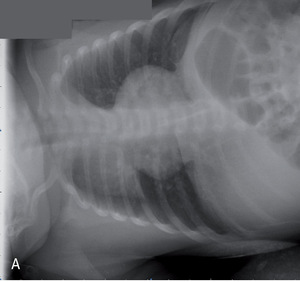

Rycina 2. Zdjęcia przeglądowe tylno-przednie (A) i boczne (B) dwutygodniowej dziewczynki z sekwestracją zewnątrzpłatową lewego płuca.